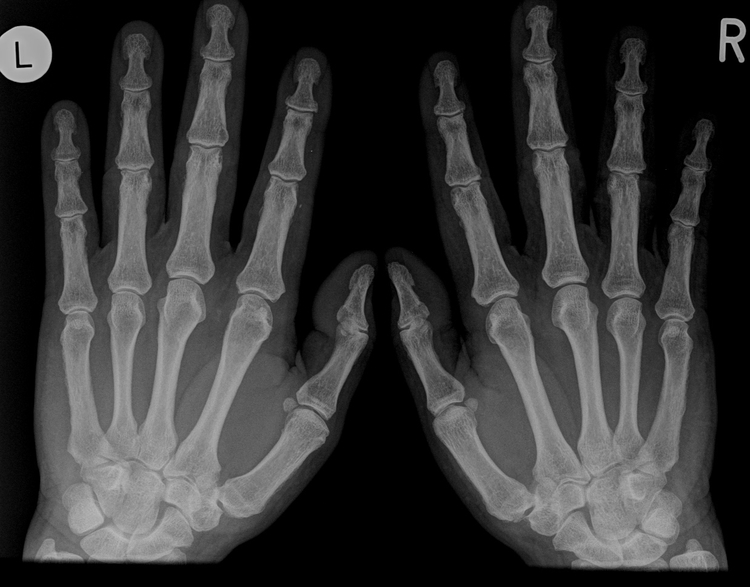

KonvRoentgen_Hand_Bild0001_6834ed9748.jpg